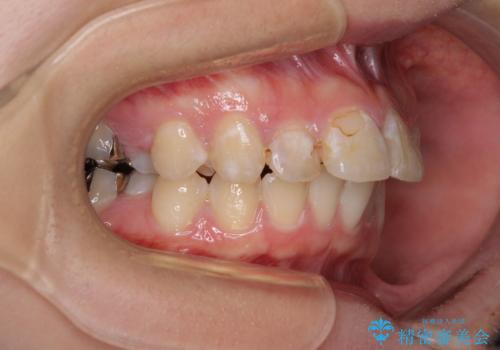

- 上の前歯の出っ歯とでこぼこの歯並びを気にして来院された患者様です。

上下顎歯列ともに前方に突出していましたが、上顎歯列がより前方位にあったため、上顎左右は第1小臼歯を、下顎左右は第二小臼歯を抜歯することとしました。

目立たないワイヤー装置にて抜歯矯正を行うこととしました。